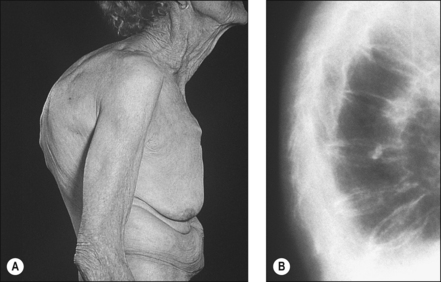

EXAMINATION

Whilst some fractures may be painfully obvious others may be detected only after careful examination and investigation. Thoracic kyphosis (Fig. 20.5A,B) may develop gradually as one vertebra after another fractures (or is compressed) or more suddenly if one or more severe wedge fractures occur. The development of the Dowager’s hump is a well recognised but late sign of osteoporosis. As this becomes more pronounced, the lower ribs impinge on the iliac crests and the abdomen protrudes. An exaggerated cervical lordosis is apparent when the patient attempts to look straight ahead. Evidence of a previous wrist fracture may also be seen such as the classical dinner fork deformity of a Colle’s fracture. A shortened externally rotated leg is highly suggestive of a fractured neck of femur.

image

Figure 20.5 (A), (B) Thoracic kyphosis. (Dowager’s hump) (A) Marked thoracic kyphosis due to multiple osteoporotic fractures in an elderly woman with (B) corresponding radiograph.

With permission Hochberg MC (2008). Elsevier.